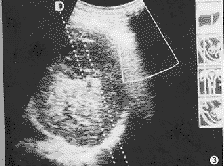

图1 治疗前超声检查示肝右叶实性肿块;

图2 图1同一病例治疗后肝右叶肿块缩小,呈条索状强回声;

例1,男性,52岁,肝癌术后3个月,发现肝内 4.0 cm×5.0 cm和 2.0 cm×3.0 cm 2个肿块,全身情况较差,食欲下降。3次微波治疗后复查肿块明显缩小,其内血流消失,活检证实肿块全部坏死,5个月后超声检查仅见小钙化点,7~8个月后经多家医院CT、B超检查未见肿块,AFP正常,患者已恢复工作,无任何不适(图1,2)。